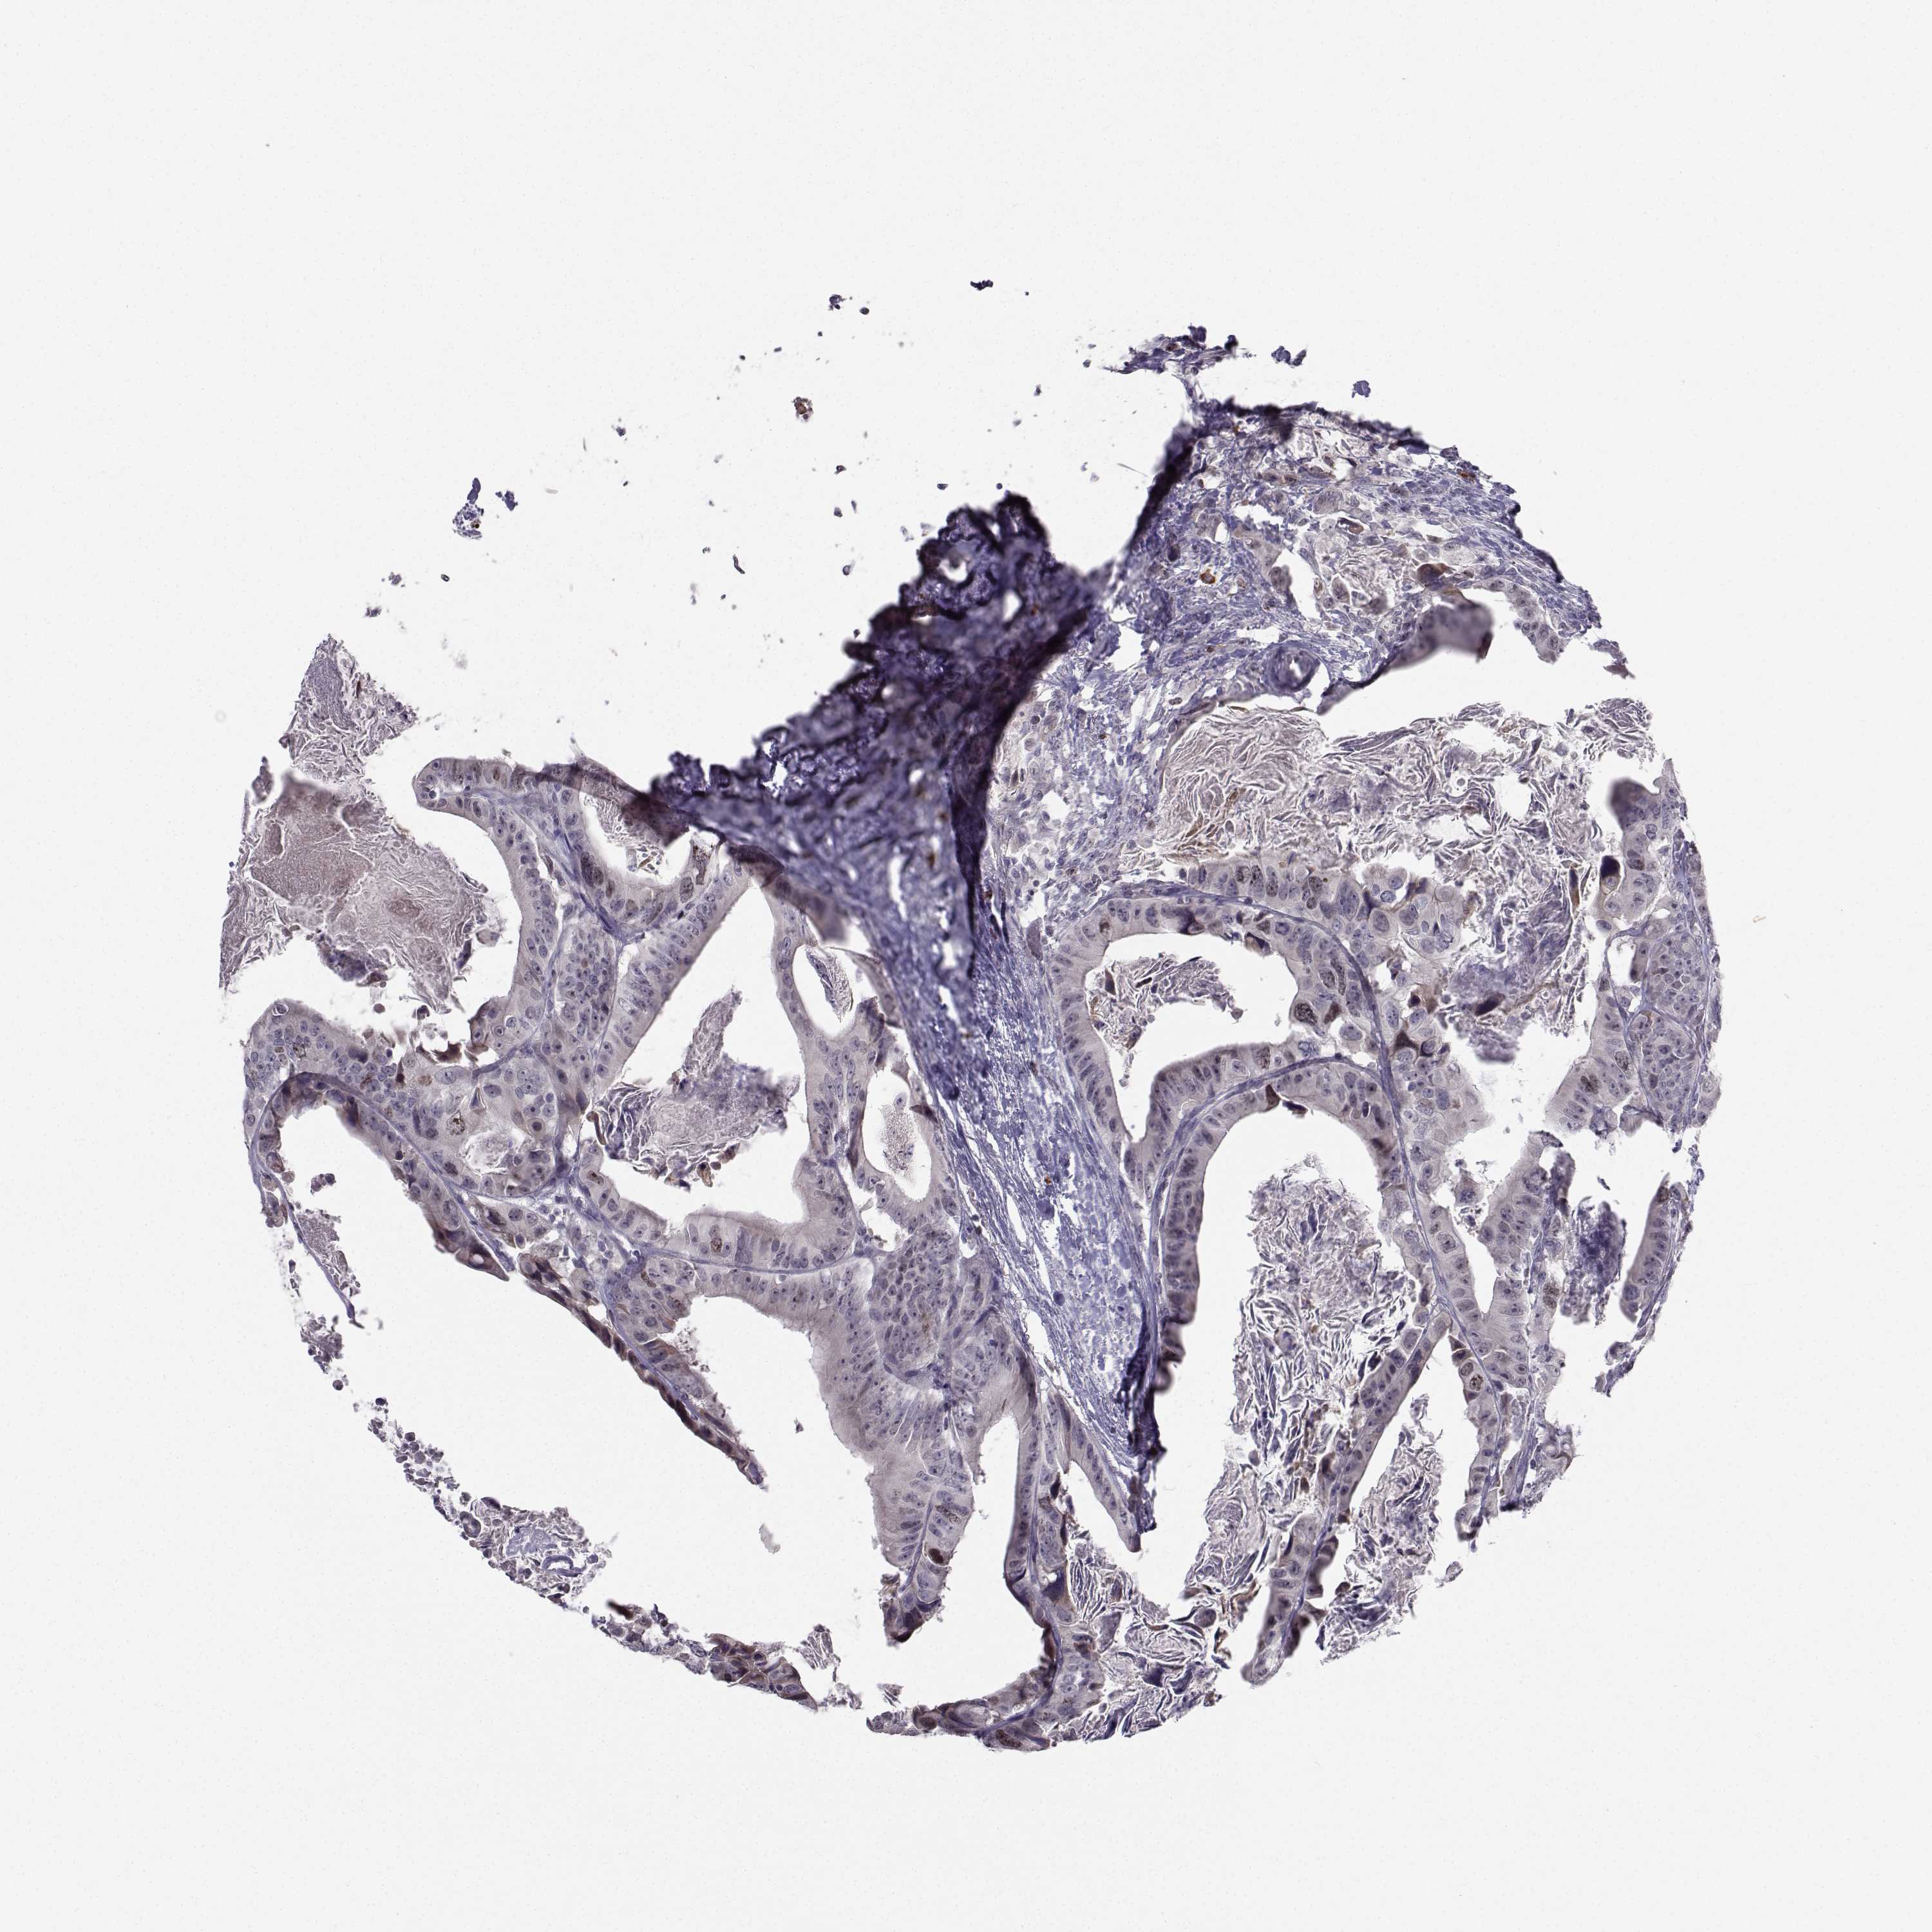

CANCER COLORECTAL CANCER Show tissue menu

Colorectal cancer

Human cancer

Colon adenocarcinoma